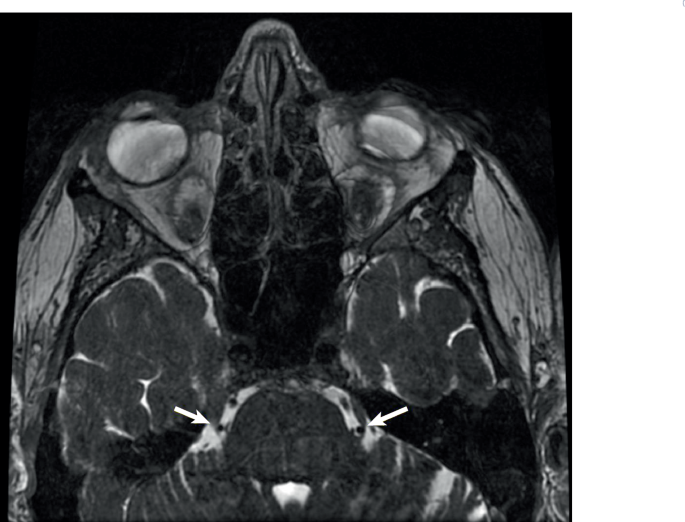

أمراض وأعراض 1 دقائق المياه البيضاء (الساد): مرض يصيب العين وأعراضه والتصنيفات والعلاجات تُعتبر المياه البيضاء أو ما يُعرف بمرض الساد من أكثر أمراض العين شيوعًا التي تُسبب ضعفًا تدريجيًا في...